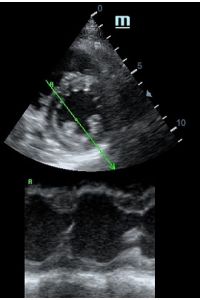

MAPSE - амплитуда движения латерального кольца митрального клапана, позволяет рассчитать фракцию выброса по формуле EF = 4.8 × MAPSE (mm) + 5.8, очень быстрый и гораздо более точный («прародитель Strain») метод чем широко распространенный метод Teicholtz. В современных приборах можно легко добавить свою формулу при отсутствии ее в стандартном калькуляторе. Главным условием является проведение линии М-режима параллельно стенке левого желудочка в апикальном четырехкамерном сечении, что легко достигается при использовании функции Free Xros.